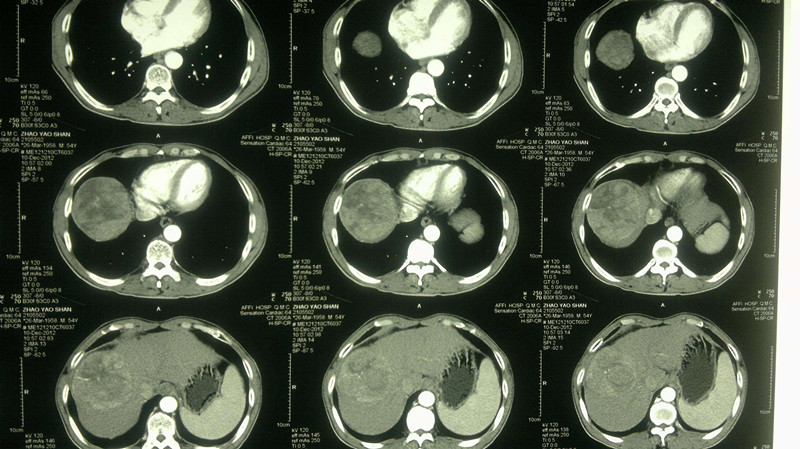

3. 肝腹水

正常人腹腔内有少量的游离腹水,一般为50毫升左右,起着维持脏器间润滑作用,当腹腔内出现过多游离液体时,称为腹水。(但是,这个病症比较少见,最常见的是肝硬化)。

6. 腹腔积液

正常状态下,人体腹腔内有少量液体(一般少于200ml),对肠道蠕动起润滑作用,超过200ml时,称为腹腔积液。比较常见的有血汗管病、肝脏病、腹膜病、肾脏病、营养障碍病、恶性肿瘤腹腔转移、卵巢肿瘤、结缔组织疾病等,都有可能诱发腹腔积液。